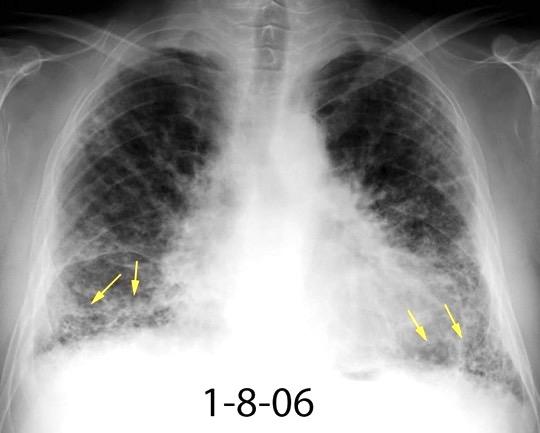

Nódulos pulmonares múltiples. (flechas verdes). Masas paratraqueales. (flechas amarillas). Dudoso ensanchamiento retrocrural (flechas negras). sigue….

Ttawfik A et al. Trans-diaphragmatic Pathologies: Anatomical Background and Spread of Disease on cross-sectional Imaging. Current Problems in Diagnostic Radiology. 2021.

T. mixto de células germinales del testículo

izquierdo Metástasis pulmonares. (flechas verdes). Ganglios paratraqueales. (flechas amarillas). Ganglios retroperitoneales (flechas negras)

Tawfik A et al. Trans-diaphragmatic Pathologies: Anatomical Background and Spread of Disease on cross-sectional Imaging. Current Problems in Diagnostic Radiology. 2021.